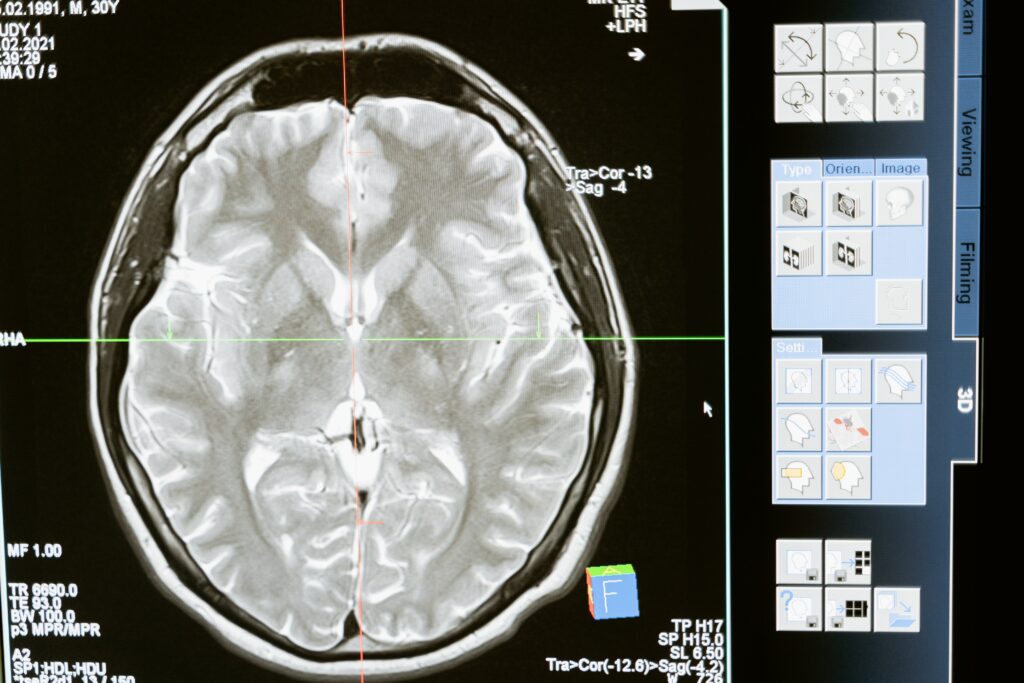

Traumatic Brain Injury: What You Need to Know

Traumatic brain injuries are the most common form of brain injury. In this term, the word ‘trauma’ means physical trauma caused by a physical blow to the head. Not all physical traumas result in the same severity or type of damage. No matter how serious or non-serious a TBI may appear, it is impossible to diagnose TBIs based on symptoms or the force of physical trauma alone. It is essential for anybody suspected of suffering from a TBI to seek immediate medical attention.